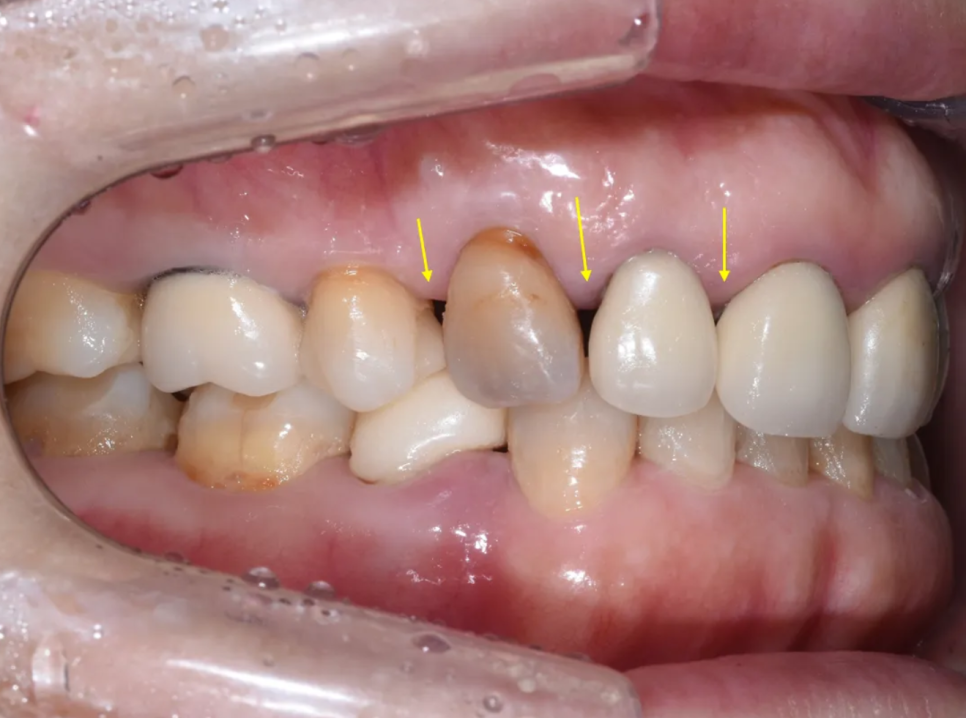

송곳니는 안쪽으로 많이 기울어져 있습니다

치아 사이 공간(블랙 트라이앵글)도 심한 편입니다

치아 사이 공간이 보이고, 송곳니가 많이 닳아 있습니다

제거 후 확인한 결과, 역시나 내부 치아에 심한 변색이 있었고 2차 충치(크라운 안에서 새로 생긴 충치)도 발견되었습니다. 하지만 다행히도 포스트-코어가 탈락하거나 치아 뿌리가 깨진 상태는 아니었기 때문에, 발치 없이 치료를 이어갈 수 있었습니다.

크라운 제거 후 내부 상태 – 심한 변색과 2차 충치가 확인됩니다